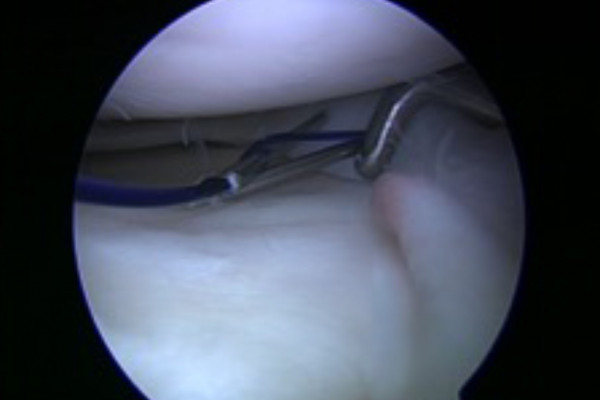

Der Meniskus ist sowohl an seinem vorderen und hinteren Ende fest mit dem Knochen des Unterschenkels verbunden. Diese Fixationspunkte werden als „Meniskuswurzel“ bezeichnet. Zwischen diesen festen Ankerpunkten spannt sich der Meniskus wie ein Trampolin auf und ist hierdurch in der Lage den auf ihn einwirkenden Kräften zu widerstehen. Kommt es zu einer Durchtrennung dieser Aufhängung (Meniskuswurzelabriss „Root Tear“) verliert der Meniskus seine Vorspannung und wird durch den Druck des Oberschenkelknochens aus dem Gelenk herausgedrückt (Extrusion). Hierdurch kommt es zu einem völligen Funktionsverlust des Meniskus ähnlich der Situation nach einer vollständigen Entfernung.

Aufgrund der Seltenheit dieser Verletzung wird sie häufig übersehen. Im Gegensatz zu einem Riss des Meniskus selbst können klassische Nähte die Funktion des Meniskus nicht wiederherstellen. Daher muss das abgerissenen Ende des Meniskus über Knochentunnel und Ankersysteme wieder fest mit dem Unterschenkelknochen verbunden werden. Auch dies kann im Rahmen einer durch einen erfahrenen Operateur im Rahmen einer Gelenkspiegelung ohne langstreckige Eröffnung des Kniegelenkes erfolgen. Nach diesem Eingriff ist eine 6 Woche Entlastung des Beines mit anschließender langsamer Aufbelastung erforderlich, um eine sichere Einheilung zu ermöglichen.

Verletzung der Meniskuswurzel